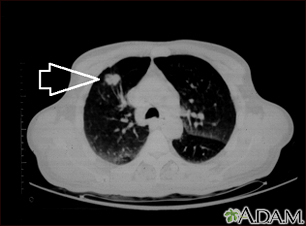

Lung mass, right upper lobe - CT scanBackLung mass, right upper lobe - CT scanThis is a CT scan of the upper lungs. This individual has a mass in upper part of the right lung (left side of picture). E-mail FormEmail ResultsName:Email address:Recipients Name:Recipients address:Message: